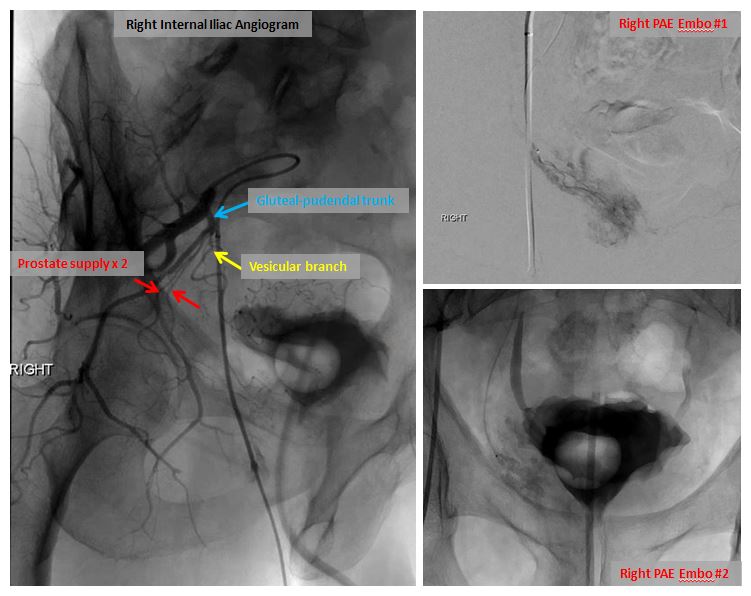

72 yo w/acute urinary retention 2/2 BPH. Remote h/o TURP. VIR consulted for PAE. Great clinical result. For more case info check out AlbanyIR.com/pae-case-1 and AlbanyIR.com/prostate-arter… for more about PAE. #IRad #PAE SIR RFS JVIR

72 yo w/acute urinary retention 2/2 BPH. Remote h/o TURP. VIR consulted for PAE. Great clinical result. For more case info check out AlbanyIR.com/pae-case-1 and AlbanyIR.com/prostate-arter… for more about PAE. #IRad #PAE <a href="/SIRRFS/">SIR RFS</a> <a href="/JVIRmedia/">JVIR</a>